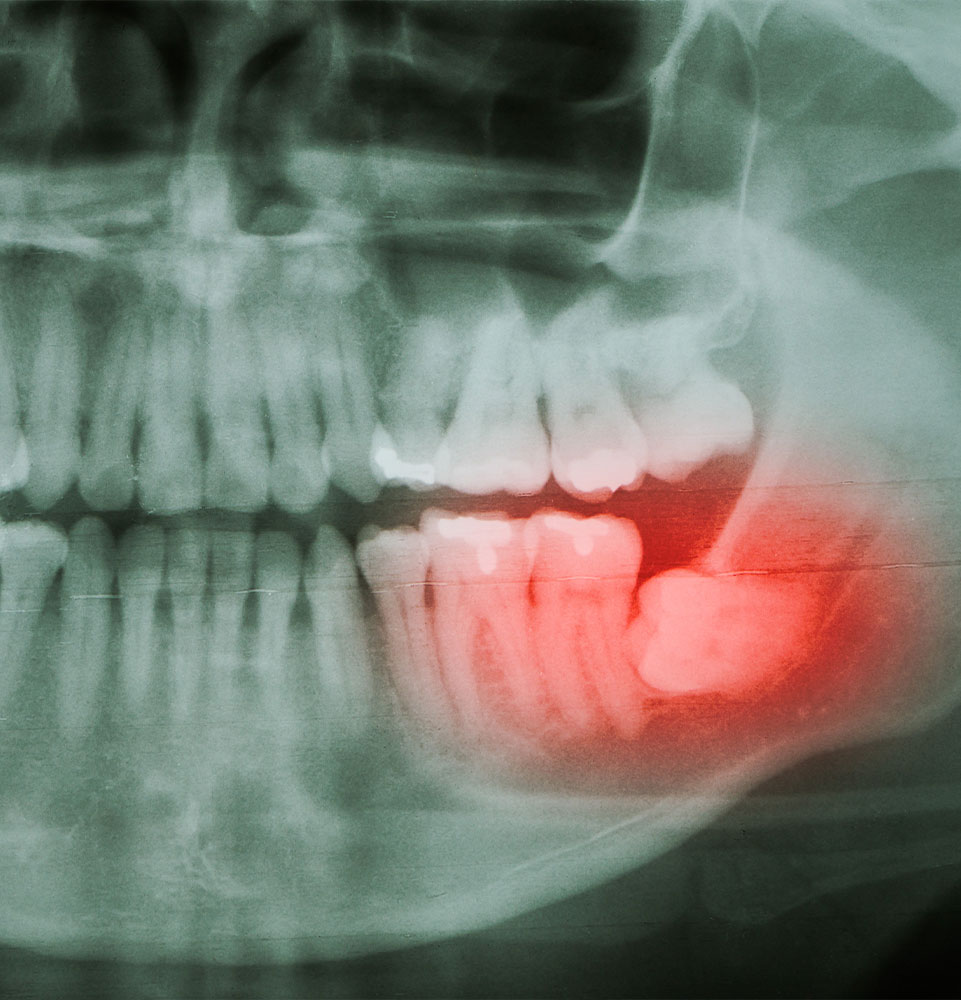

Wisdom teeth typically emerge between 16 and 25 years of age. Although it’s best to remove them in your teen and early adult years, wisdom teeth may not cause pain until later in life. Many patients don’t experience symptoms, even if they have impacted teeth. When wisdom teeth are impacted, they are blocked and are unable to fully erupt. We use our i-CAT® Cone Beam CT imaging technology to capture three-dimensional and detailed images of your teeth and their surrounding oral structures to grasp a thorough understanding of your current state before recommending your custom care. If impacted wisdom teeth extractions are advised, we will carefully remove them while you are comfortably sedated and provide detailed instructions for how to encourage healing.

Common Symptoms of Impacted Wisdom Teeth

- Advanced Periodontal Disease

- Impacted Wisdom Tooth

- Severe Facial Trauma or Damaged Teeth

- Retained Baby Teeth

- Extensive Bone Loss

- Preparation for Dental Implants